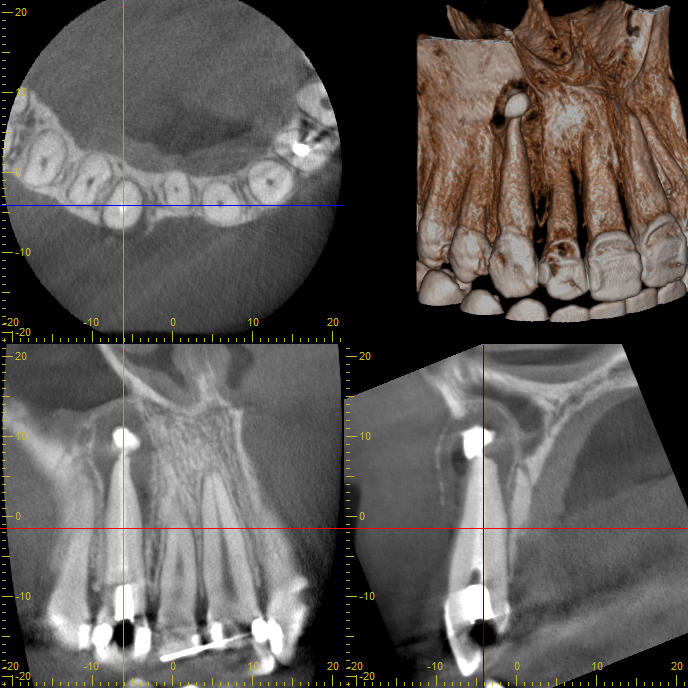

薬を詰めたところ

治療から2週間後には腫れと痛みが消失し、違和感も解消。

経過観察として3ヶ月ごとにCT撮影を実施したところ、嚢胞は次第に縮小し、最終的に完全に消失が確認されました。

結果として、抜歯や外科処置を行わず、自然治癒へ導くことができました。

1年後経過写真※嚢胞は消失している